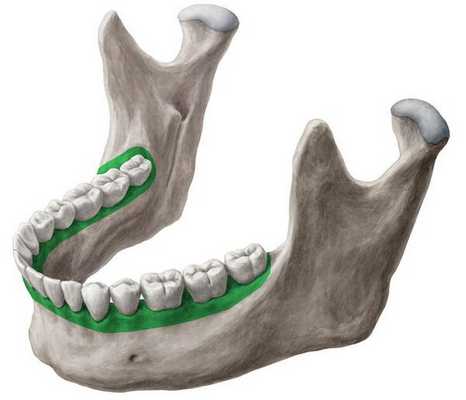

Аномалии зубных рядов - это врожденные или приобретенные нарушения формы и длины нижней и верхней зубных дуг, характеризующиеся неправильным расположением (скученностью, асимметрией, транспозицией, изменением количества и пр.) зубов. Сопровождаются неправильным прикусом, нарушениями смыкания зубов, неудовлетворительной эстетикой улыбки. Диагностируются аномалии зубных рядов на основании признаков, выявленных во время стоматологического осмотра, изучения диагностических моделей и рентгенологических данных. Лечение аномалий зубных рядов состоит в восстановлении их нормальной формы и длины при помощи ортодонтической терапии, методов хирургической и ортопедической стоматологии.

Аномалии зубных рядов - обобщенное название ряда патологий формы и длины зубных дуг, оказывающих влияние на эстетику улыбки человека и функциональность зубочелюстной системы. Нормальная анатомическая форма зубного ряда верхней челюсти напоминает полуэллипс, а нижней - параболу. Аномалии зубных рядов могут характеризоваться удлинением либо укорочением, сужением или расширением зубных дуг на определенных участках челюсти. Аномалии зубных рядов проявляют себя скученным или неправильным расположением зубов (оральным или вестибулярным наклоном, поворотом по оси и т. д.), неполной адентией, тремами, диастемами, гиперодонтией и т. п. Нарушения формы и длины зубных рядов могут развиваться независимо друг от друга. В таких случаях часто наблюдается неправильная окклюзия пар зубов-антагонистов.

Аномалии зубных рядов различаются по отношению к трансверзальной (горизонтальной), сагиттальной (передне-задней) и вертикальной плоскости.

1. Трансверзальными аномалиями называют сужение или расширение зубных дуг, характеризующееся уменьшенным или увеличенным расстоянием между медиальной плоскостью и латерально стоящими от нее зубами. Среди нарушений, относящихся к данному виду, встречаются следующие формы: